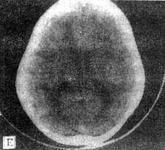

球形細(xì)胞腦白質(zhì)營(yíng)養(yǎng)不良即球形細(xì)胞型白質(zhì)營(yíng)養(yǎng)不良(globoid cell leukodystrophy,GLD),又名Krabbe白質(zhì)營(yíng)養(yǎng)不良癥、Krabbe病、Krabbe急性嬰兒型腦硬化、球形白細(xì)胞發(fā)育障礙癥、先天性全身肌發(fā)育不全、類球狀細(xì)胞型白質(zhì)腦病、類球狀細(xì)胞型彌漫性硬化癥、Krabbe綜合征等。為常染色體隱性遺傳,是β-半乳糖苷酶的缺乏或其活性減低所致腦脂質(zhì)沉積病。